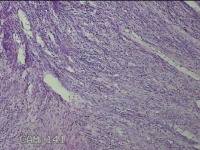

子宫肌瘤结节

多发性子宫肌瘤 继发性不孕症 子宫Ⅰ度脱垂 高脂血症 胆囊息肉

一般病史

发现子宫肌瘤4年余,继发不孕3年。

标本名称

大体所见

灰白暗红色圆形肿物10x9x2.8㎝九个,表面糜烂,切面均为灰白色结节状或编织状,质中。

良性病变。

考虑平滑肌瘤。